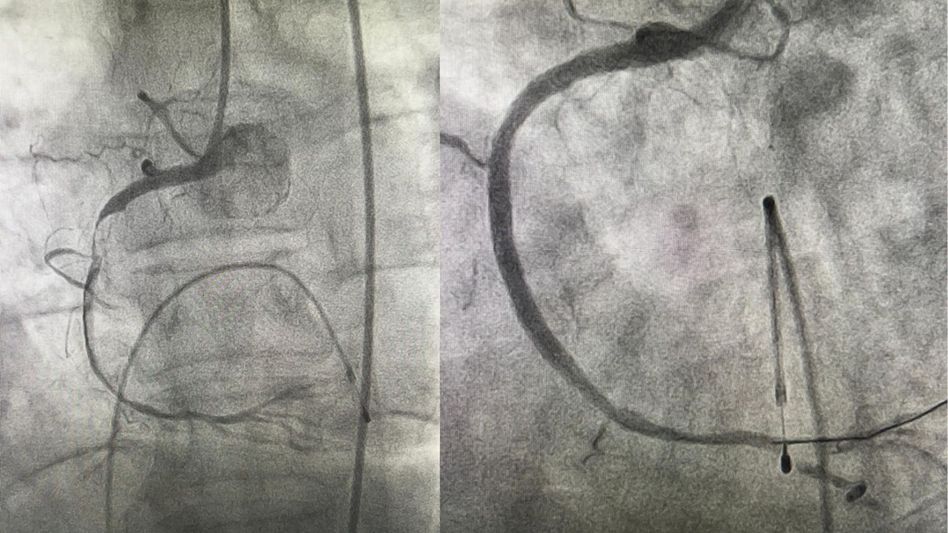

The medical team, led by Dr Rinchin Dorjee Megeji, Associate Professor of Cardiology, and Dr Tony Ete, Assistant Professor of Cardiology, swiftly took action. First, a temporary pacemaker (TPI) was implanted, followed by a coronary angiogram (CAG) of the left coronary artery (LCA), which revealed significant disease in the left anterior descending artery (LAD).

However, before the right coronary artery (RCA) could be accessed, the patient developed ventricular tachycardia (VT) followed by cardiac arrest. The team promptly administered a defibrillator shock and initiated cardiopulmonary resuscitation (CPR). Simultaneously, they managed to hook the RCA and perform a CAG, which showed near-total occlusion of the culprit proximal RCA.

The medical team proceeded with ballooning and stenting of the proximal RCA. During the stenting process, the patient experienced another episode of VT, requiring an additional defibrillator shock. Once the stenting was completed, the patient's vitals began stabilising, and the VT gradually disappeared.